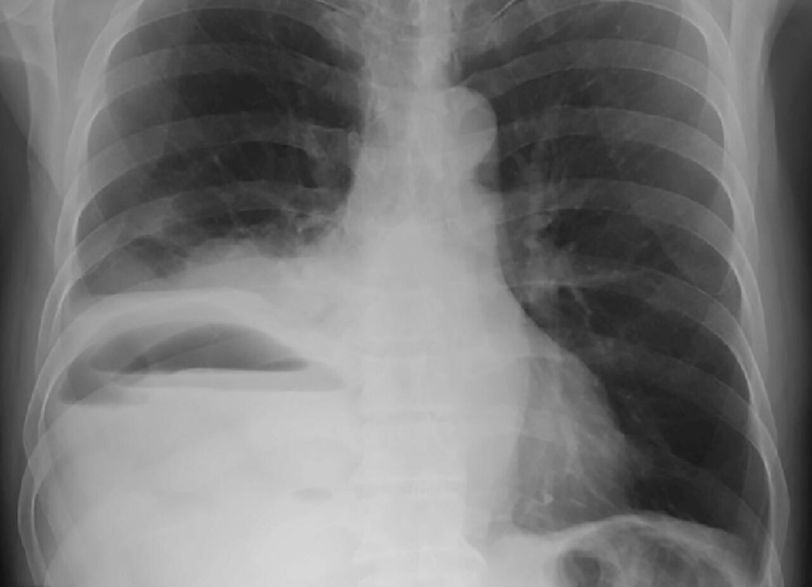

Diagnosis???

Empiema of right pleural cavity

Pleural effusion

Rt.sided empyema